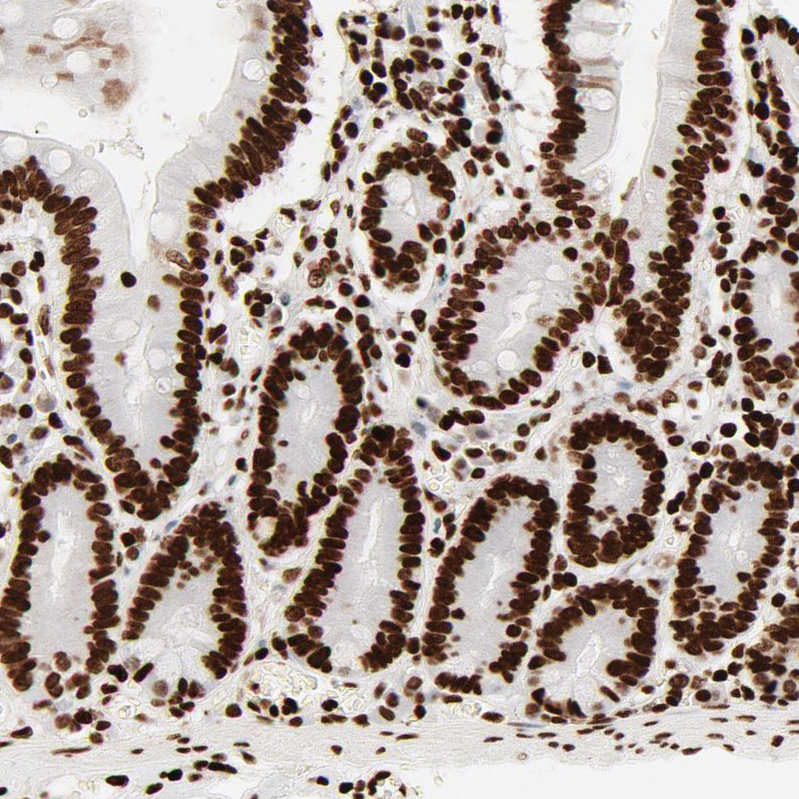

Immunohistochemical staining of human bone marrow shows strong nuclear positivity in hematopoietic cells.